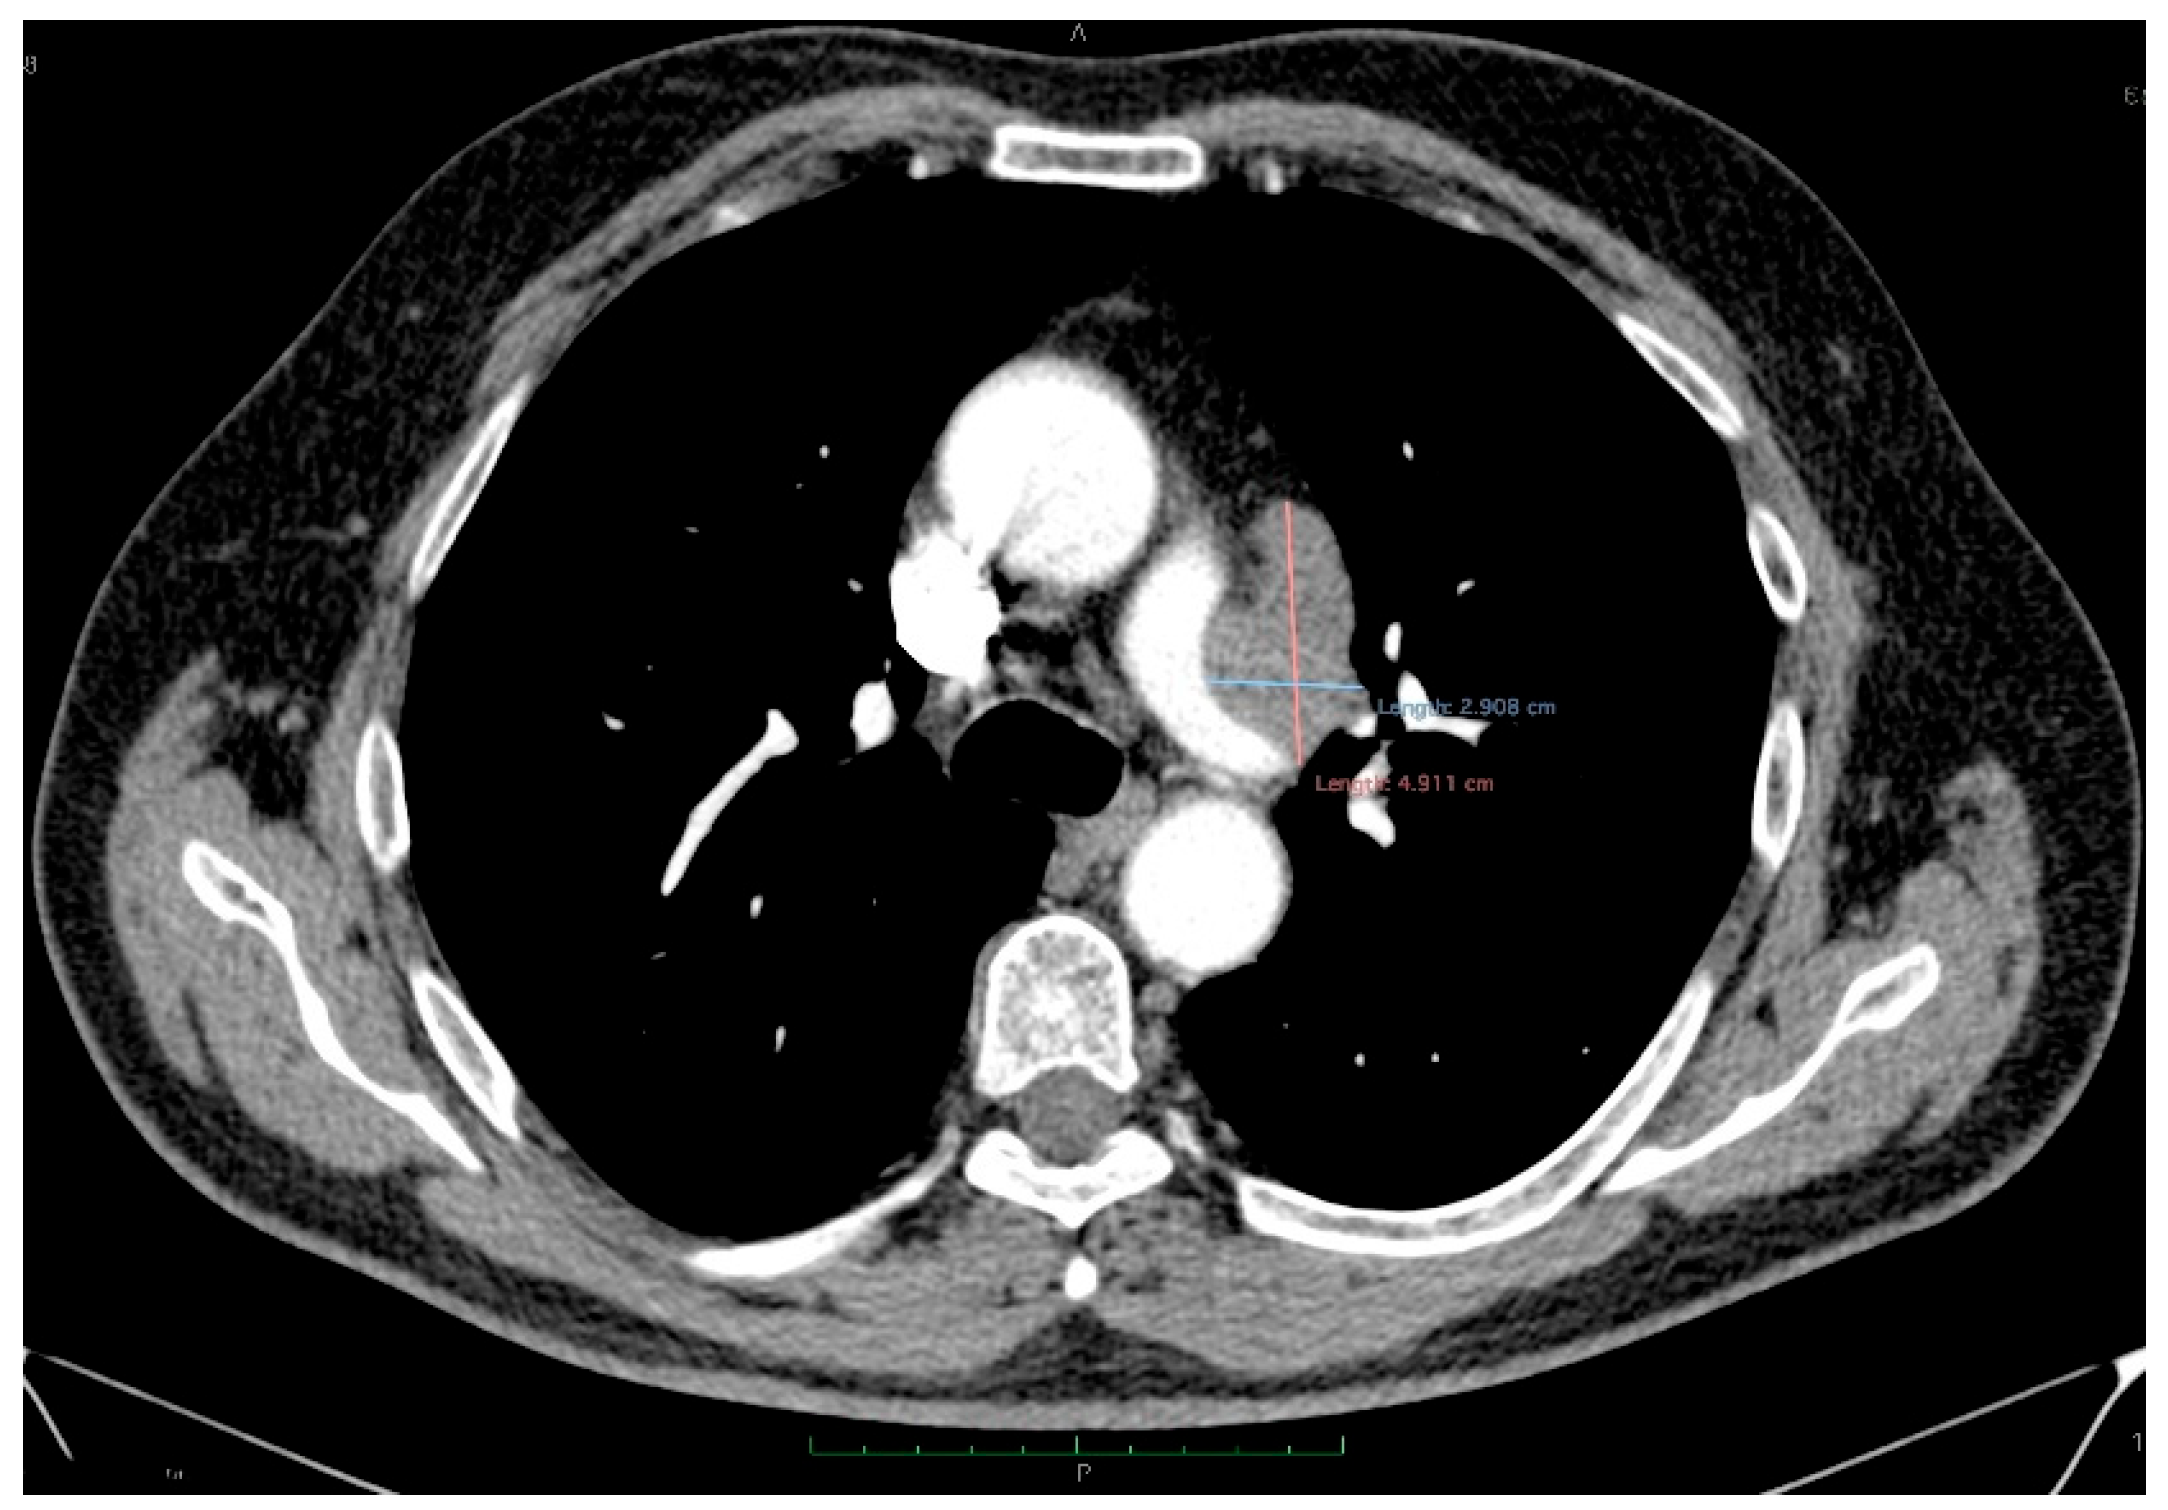

The abdominal contrast-enhanced CT scan further revealed multiple hepatic hypodense nodular lesions, measuring between 1 cm and 3 cm (Figure 6 and Figure 7).

Figure 6.

Contrast-enhanced abdominal CT (axial, non-contrast phase—left, arterial phase—center, and portal venous phase—right) shows liver sections with hypodense nodule in IVa hepatic segment exhibiting arterial-phase enhancement similar to background parenchyma and washout on the portal venous phase, measuring 1–3 cm (arrows).